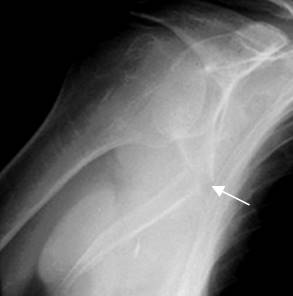

Fig 11. Fractura de escápula.

Rx tangencial de hombro. Fractura angulada del tercio medio de la escápula.